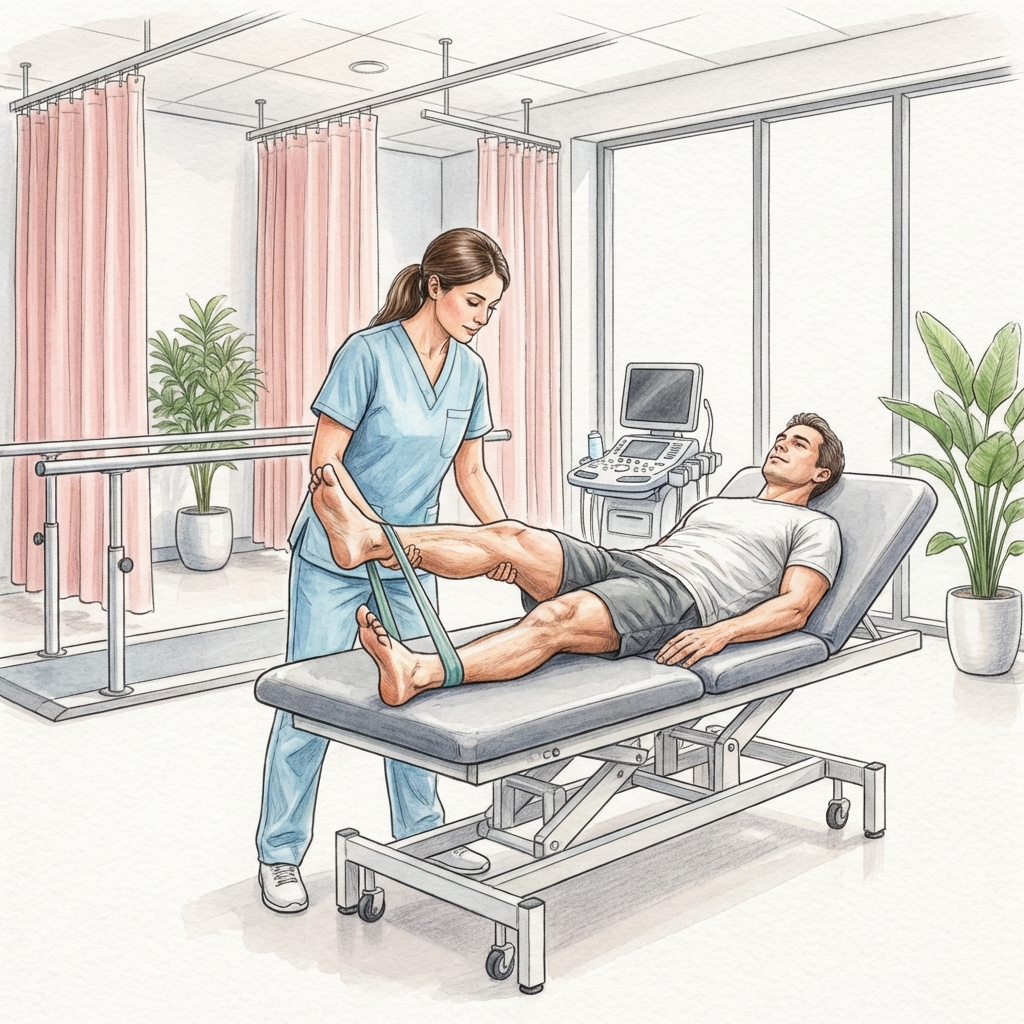

Các phương pháp dưới đây được phối hợp linh hoạt theo từng giai đoạn phục hồi, không áp dụng máy móc một phác đồ chung cho mọi trường hợp. Việc cá nhân hóa can thiệp giúp giảm quá tải, tăng khả năng đáp ứng điều trị và duy trì kết quả ổn định sau khi kết thúc chương trình.

- Kiểm soát đau và viêm giai đoạn sớm (manual therapy, vật lý trị liệu hỗ trợ)

- Tập phục hồi tầm vận động khớp và mô mềm có kiểm soát

- Tăng sức mạnh cơ lõi - cơ ổn định khớp theo chuỗi vận động

- Proprioception, thăng bằng và phản xạ thần kinh - cơ